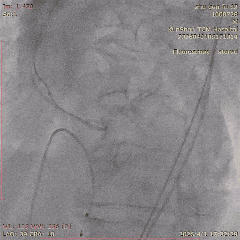

第一阶段,团队先为张老先生进行冠脉造影及介入治疗。结果显示,患者左前降支存在慢性完全闭塞病变,并伴有严重扭曲和钙化,常规处理难度较大。

在充分评估后,团队先对病变部位进行旋磨处理,再完成后续介入治疗。术后,张老先生病情稳定,未再出现心绞痛发作,也为后续主动脉瓣置换争取了更安全的条件。

CAG-LCA-1

CAG-LCA-2

CAG-RCA-1

CAG-RCA-2

▲冠脉造影:LAD-CTO病变,严重扭曲、钙化

▲开通,扭控MC

▲旋磨

▲术后